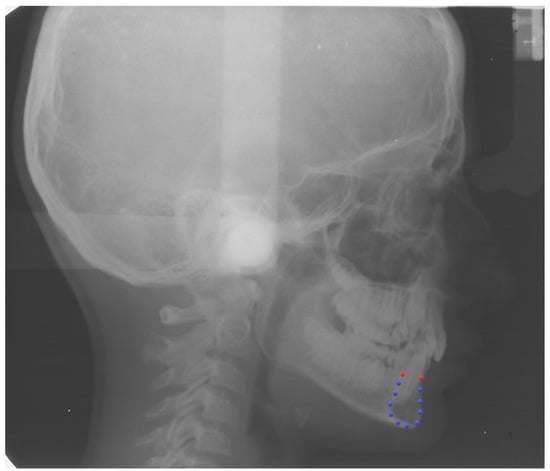

A single continuous curve was digitized following the outline of the symphysis on each lateral cephalogram to assess the general outline (View box 4.1 Dhal software, Kifissia, Greece). As geometric morphometrics does not allow the use of curves, we placed twelve landmarks on the curve of the symphysis. Firstly, two points were identified at the vestibular superior (VS point) and lingual superior (LS point) margins of the cortical bone of the symphysis. Since these two points derived from the specific anatomy of the symphysis and were easily identifiable in each specimen, they were considered homologous and used as fixed points or landmarks. The remaining ten points were randomly placed along the curve, then distributed uniformly using a specific feature of the software and allowed to slide along the curve to minimize the bending energy as semi-landmarks [11] (Supplementary Table S1). By repeating this process 5 times iteratively, we reached a position that was considered homologous between all the specimens and that allowed us to consider the 10 semi-landmarks as fixed points (Figure 1) [12].

Figure 1.

Example of a longitudinal cephalogram of recruited patient from the American Association of Orthodontists Foundation (AAOF) Craniofacial Growth Legacy Collection. Red dots = fixed landmarks (VS point and LS point); blue dots = semi-landmarks.